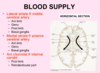

label the image:

what do the communicating vessels act as?

- The communicating vessels in the circle of willis act as potential routes for collateral circulation

Describe the overall pattern of blood supply to the different regions of the cerebral hemispheres

Which arteries (vertebral/ internal carotid) give which cerebral arteries?

- Anterior cerebral artery does the anteromedial surface of the cerebrum

- Middle cerebral artery does most of the lateral surface of the cerebral hemispheres, up to superior/ middle temporal gyrus of the temporal lobe.

- Posterior cerebral artery supplies the lateral and medial regions of the posterior cerebrum.

- Remember the internal carotid arteries give off the ACA and MCA.

- The vertebral arteries unite as the basilar, then bifurcate to give the PCA.